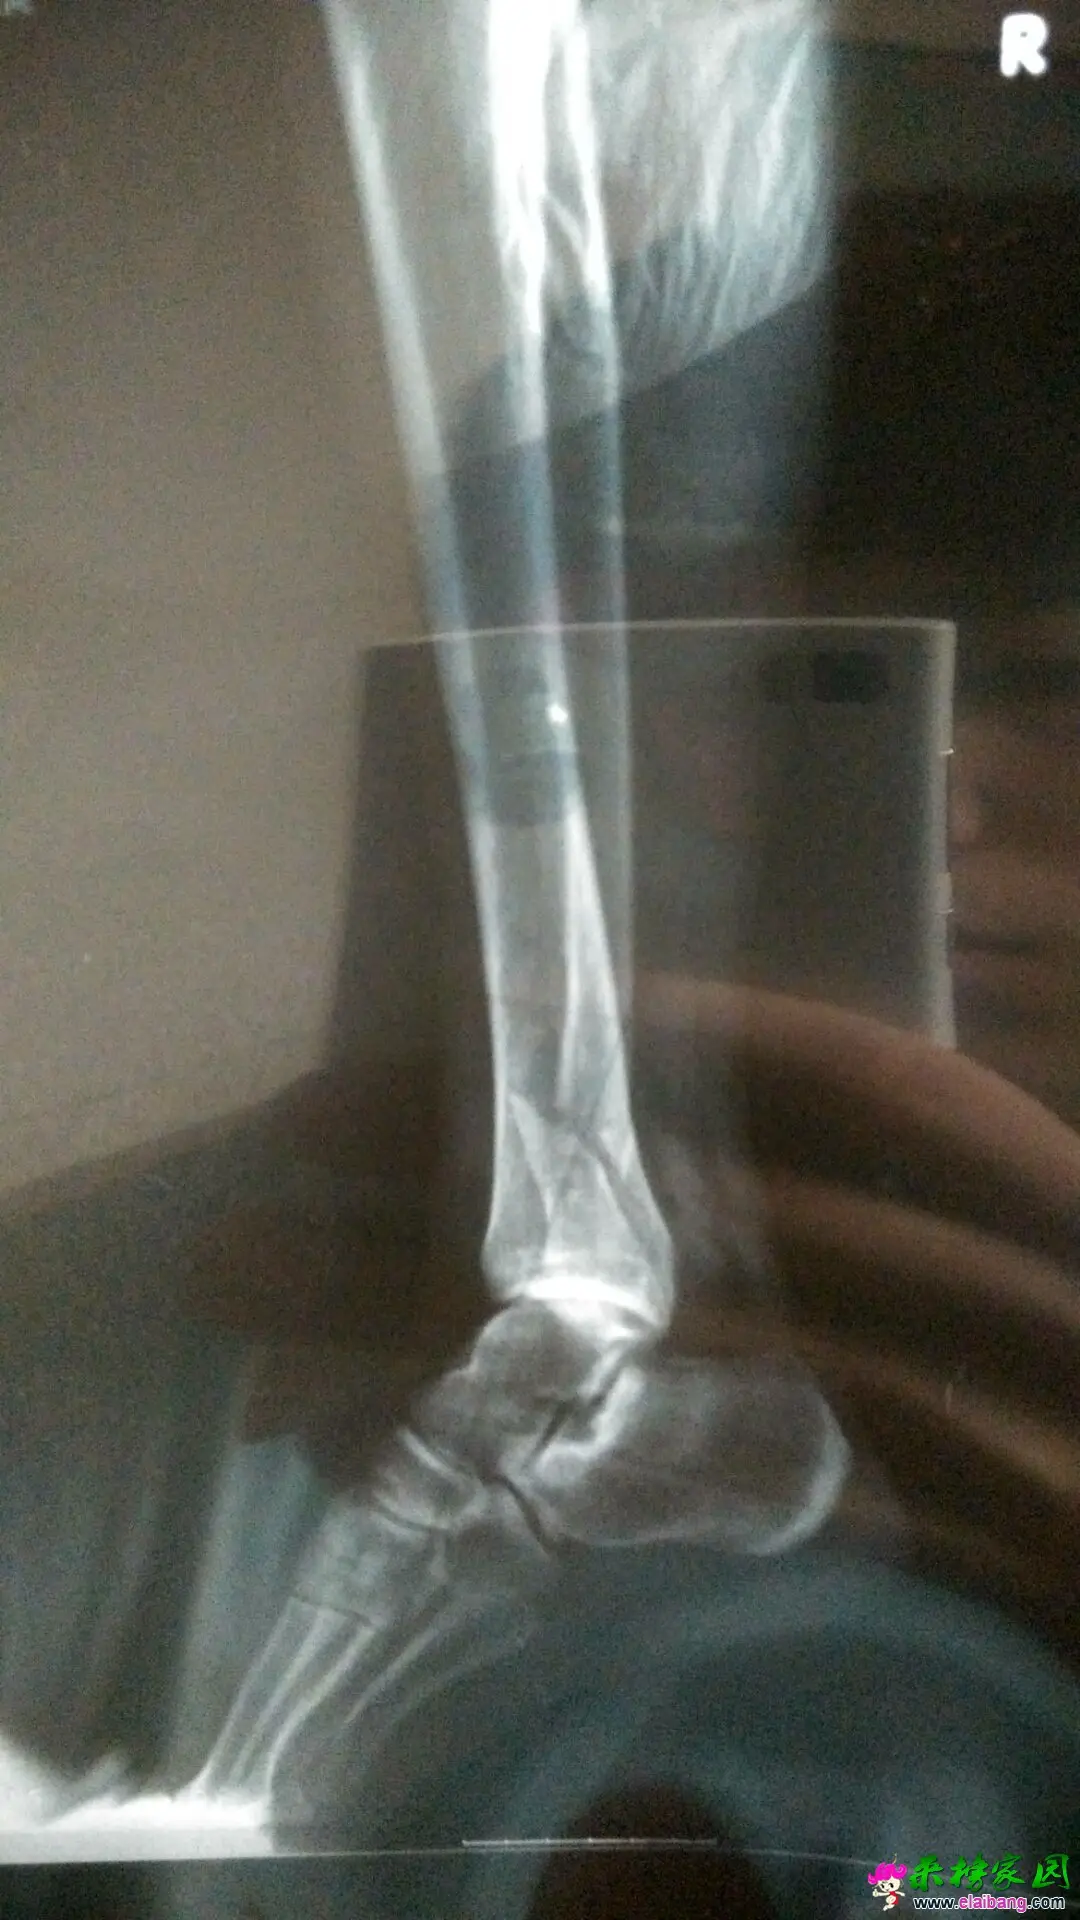

5月14日更新,医院发来的骨折拍照

11日上午,储诚才在自己农田里用农机耕田的时候,不幸被农机的车轮碾过穿有皮靴的脚背,储诚才自己也被困在泥田里起不来。附近的村民看到后来了六个人花了近2个小时才将他从泥田里拉扯起来。他被人背着到旁边的树林休息的时候还没有感觉到事情的严重性,当脱掉胶靴的时候,露出的白骨让所有现场的人都惊呆了:从脚背到小腿的关节处就剩一点皮肉连在了一起,小腿的白骨都已经露了出来。或许是太疼了,当时的他竟然感觉不到任何的疼痛。热心的村民赶紧将他送到了县医院,后紧急转院到了第三人民医院。

今天获悉,储诚才已经动了第一次手术,现在要看手术后的恢复情况,医生说这次手术后还需要第二次手术,恢复得好的话,可以下地走一小段路,但是受力很大的农活之类肯定是不行了。他们一家去年做的房子还没有装修,尚且欠了不少的外债,大儿子在大学读书也是正值用钱的时候。这次手术保守估计要十多万的手术费用及后期护养费用。羊河村村委了解他们家的具体情况后,委托来榜家园将此事通过网络平台传播,希望能有好心的人帮帮他们度过难关。他是家中的顶梁柱,我们一起帮助他站起来!